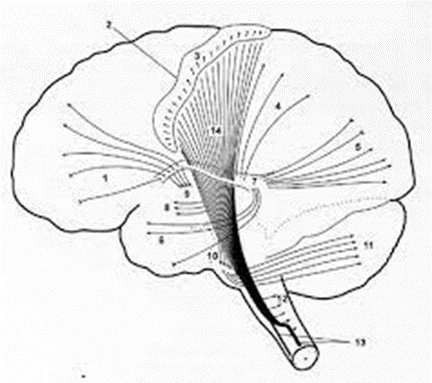

Projection fiber(투사섬유)

대뇌 피질에서 하부에 있는 뇌간(중뇌, 교, 연수)과 척수 사이를 연결하는 신경섬유로 대뇌 피질을 향해 부채꼴 모양으로 퍼져 있어 방사관 corona라고 한다. 대뇌 피질로 올라가는 상행성 감각 섬유와 대뇌 피질에서 말초로 가는 하행성 운동 섬유로 구성되어 있다.

속섬유막 장애

속섬유막은 앞다리 · 무릎 · 뒤다리로 나누어진다. 추체로 즉, 상위운동신경세포(겉질핵로와 겉질척수로)는 뒤다리를 통과하는데, 그 후에는 시상과 대뇌겉질 지각구역(마루엽)을 연결하는 위시상각이 뒤다리를 통과한다. 다시 그 후에는 시각로부챗살이 통과하고 있다. 이들이 손상을 입으면 다음과 같은 증상이 나타난다.

반대쪽 :

① 편마비(얼굴 · 혀를 포함) (←추체로장애)

얼굴 상부에 마비는 나타나지 않는다. 또 다리보다 팔 쪽에 강한 마비가 오는 경우가 많으며 마비는 강직성이다.

② 심부 힘줄반사의 항진 (←추체로장애)

③ 병적반사(+) (←추체로장애)

④ 표재반사(-) (←추체로장애)

②, ③, ④는 추체로 징후라 불린다.

팔이 굽혀지고 다리가 펴지며, 첨족(dangle foot)이 특징적으로 나타나는 Wernicke-Mann 자세(편측성 겉질제거경직)를 취한다

후부까지 손상을 입으면,

⑤ 편측 지각마비(얼굴을 포함) (←위시상각장애)

⑥ 같은 쪽 반맹 (←시각로부챗살장애)

또 우위반구에 장애가 생기는 경우에는 언어상 실증이 발생한다.

⑦ 언어상 실증 앞맥락동맥(← 속목동맥의 가지)에 의해 지배되고 있지만, 실제로는 속섬유막에 인접하는 조가비핵의 가쪽을 지배하고 있는 렌즈핵 줄무늬체 동맥(← 중간대뇌동맥)의 장애에 의해 2차적으로 장애를 받는 경우가 많다고 알려져 있다. 이 동맥은 대뇌겉질에 영양을 공급하는 것은 아니므로 이곳이 장애를 받아도 직접적으로는 Broca 중추나 Wernicke 중추가 존재하는 대뇌겉질이 장애를 받는 것은 아니다.

그러나 이 동맥이 파손되어 출혈이 일어났을 때에는 겉질 밑의 신경섬유가 장애를 받을 가능성이 생긴다. 즉, 고차 신경기능에서 말한 순수운동언어상 실증이나 순수 감각언어상 실증을 초래할 가능성이 있다. 조가비핵출혈은 뇌출혈 중에서 가장 발생하기가 쉽다.